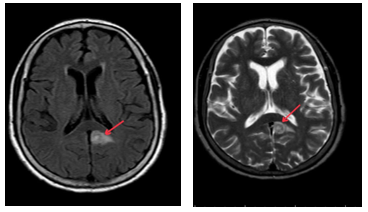

-         Cắt lớp vi tính ngực (Bệnh viện Bạch Mai): phổi trái: phân thùy S3 có khối tỷ trọng tổ chức kích thước 18x26mm, bờ không đều ranh giới không rõ với màng phổi trung thất, lân cận có vài dải xẹp. Nốt bán đặc nhỏ thùy dưới đường kính khoảng 4mm. Vài hạch trung thất đường kính <10mm. Xương đòn trái có đậm độ không đều kèm dày vỏ xương đoạn 1/3 trong. Khoang màng phổi hai bên không thấy dịch –khí.

Hình 3: Cắt lớp vi tính lồng ngực sau 3 tháng điều trị bằng Osimertinib cho thấy khối u phổi trái tại phân thùy S3 giảm kích thước (mũi tên đen), hạch trung thất thoái triển, tràn dịch màng phổi giảm.

Nhận xét: Sau 3 tháng điều trị đích bằng Osimertinib (80mg/ngày), bệnh nhân ghi nhận đáp ứng điều trị rõ rệt. Lâm sàng cải thiện tốt. Trên cắt lớp vi tính lồng ngực, khối u phổi trái giảm kích thước, hạch trung thất thoái triển, tràn dịch màng phổi giảm đáng kể. Theo tiêu chuẩn RECIST 1.1, bệnh nhân được đánh giá đáp ứng 1 phần. Sau 6 tháng điều trị đích, bệnh nhân cải thiện rõ về mặt lâm sàng, toàn trạng ổn, xét nghiệm chất chỉ điểm khối u giảm rõ rệt, cắt lớp vi tính bụng, não không ghi nhận tổn thương thứ phát. Kết quả cho thấy hiệu quả kiểm soát bệnh kéo dài của Osimertinib.